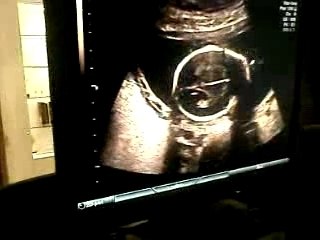

Ecografia Ostetrica 20 settimane